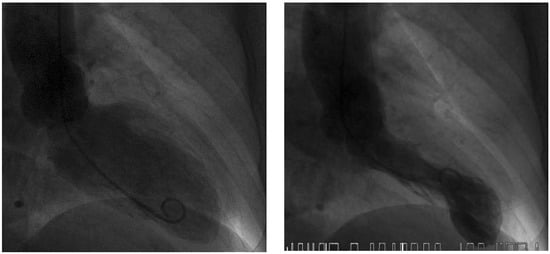

Figure 6. Echocardiographic follow-up after 4 weeks: End-diastolic (left side) and endsystolic (right side) frames of parasternal long axis (top row) and four-chamber view (bottom row). Left ventricular function recovered completely after 4 weeks.